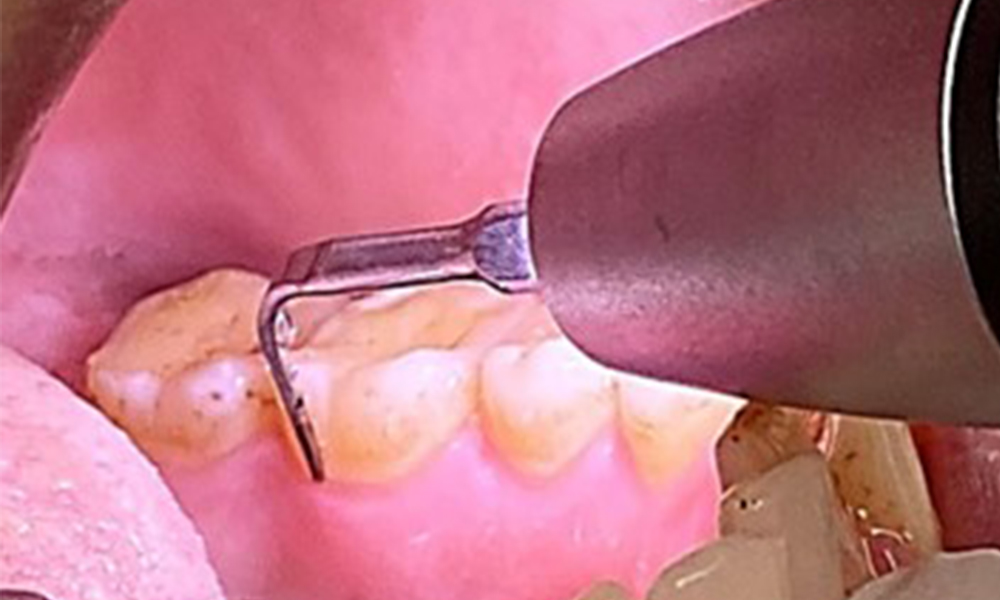

Due to the otherwise favourable general medical condition, the needs determined during the intraoral examination will be decisive for their treatment. It will be essential to periodically determine the probing depths. Gingival bleeding decreases in smokers, which is why the clinical diagnosis of periodontitis can only be made by probing (Fig. 7). Placing exclusive focus on the determination of bleeding indices may obscure existing periodontitis or gingivitis. (5)

Pocket probing (BOP) with depiction of tooth 36 lingual

Fig. 7 Pocket probing (BOP) with depiction of tooth 36 lingual, © Dr R. Krapf